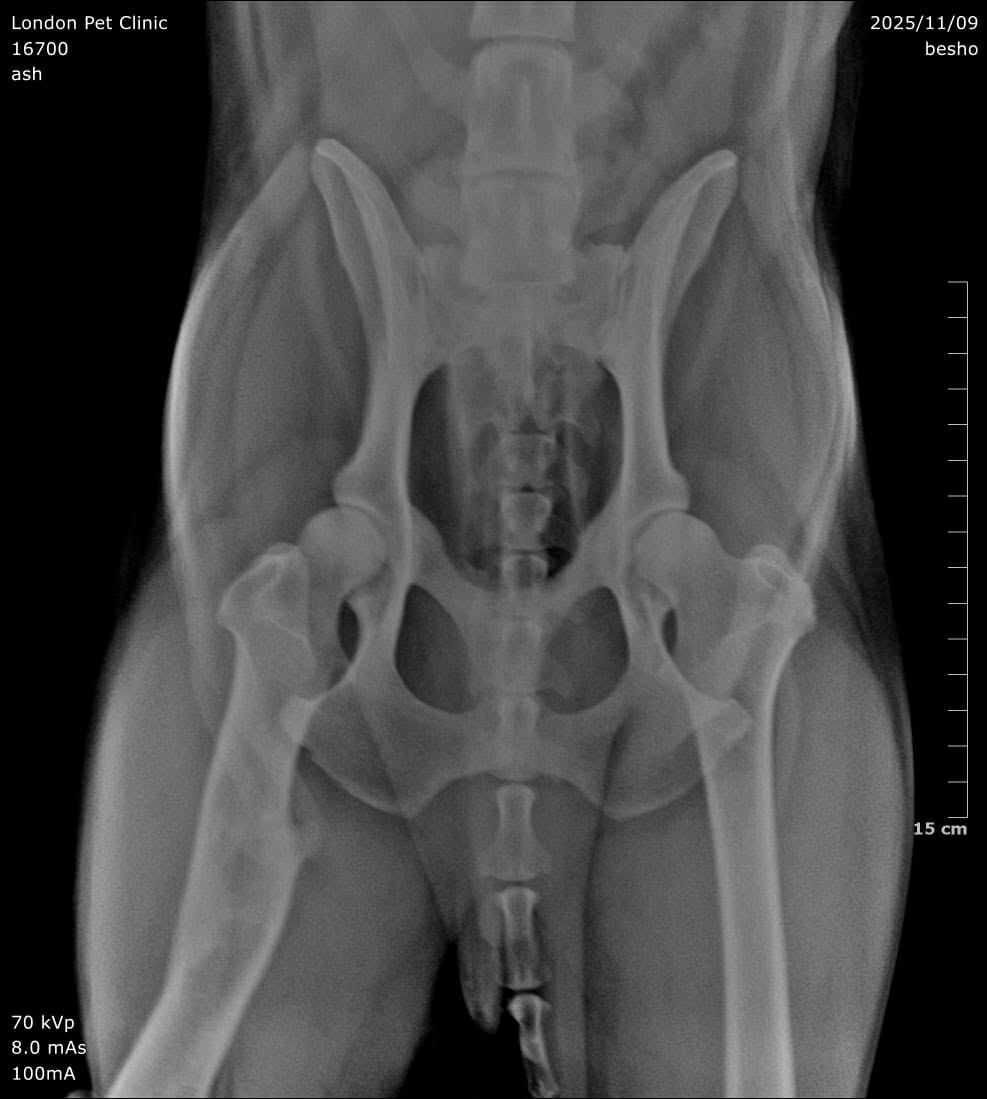

Old orthopedic injuries: malunion of the femur and tibia with patellar luxation

Radiographs